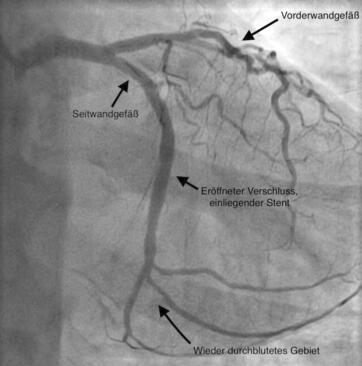

Die Koronarangiographie (Darstellung des Herzkranzgefäßes mittels Röntgenkontrastmittels) führt zum Nachweis von Einengungen, Verkalkungen und Verschlüssen der Herzkranzgefäße. Sie ist eine wichtige Voraussetzung, um zu entscheiden, ob eine medikamentöse Therapie, eine Ballonaufdehnung (PTCA) oder eine Bypassoperation sinnvoll ist. Im Falle einer Einengung des Herzkranzgefäßes kann diese in der gleichen Sitzung mit Ballonaufdehnung (PTCA/PCI) und Stent (Gefäßstütze) behandelt werden.

Die früher verwendeten konventionellen Metallstents bilden heutzutage eine große Ausnahme und werden nur in speziellen Fällen implantiert. Die überwiegende Mehrheit aller Stents sind medikamentenbeschichtete Stents, die eine überschießende Proliferation von Zellen, welche zu einer Wiederverengung des Gefäßes führen würden, hemmt.